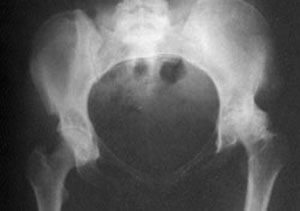

Häzirki wagtda süňk inçekeseli yüze çykyş ýygylygy boýunça öýkenden daşary döreýän inçekeseliň görnüşleriniň arasynda dördünji orny eýeleýändir.

Eger inçekesel ýokanjy oňurgany we süňk bogunlaryny zeperlendiren bolsa, syrkawa süňk inçekeseli diýen kesel kesgidi goýulýar. Keseliň bu görnüşi Kohuň  taýajygynyň ilkinji inçekesel ojagyndan, gan arkaly,  süňk ýiligine geçmegi bilen döreýär we  on ýaşa çenli çagalarda has ýygy duş gelýär. Süňk inçekeseli  köplenç süňk ýiliginiň ahyrky böleklerinde (epifizde) ýaýbaňlanyp başlaýar. Soňra ol bogny örtýän nemli haltajygyna (sinowial haltajygy) we bogun kekirdewüklerine geçýär.